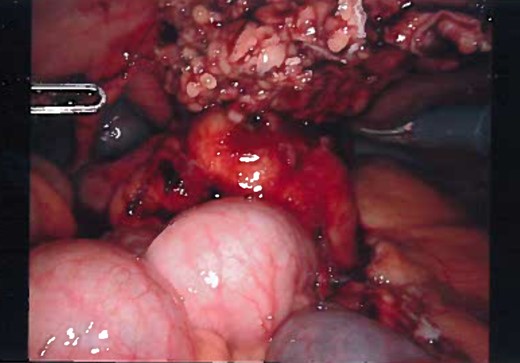

Patient was administered general anesthesia with placement of endotracheal tube. She was placed in lithotomy position (stirrups), both arms tucked at sides, strap secure across chest and a bair hugger (warmer) was placed around upper chest/head/neck area. Our patient was prepped with betadine for a vaginal/perineal prep and chloroprep was used on the abdomen. After sterile draping of the patient, and official time-out with all in agreeance, the Urologist evaluated the bladder with a cystoscopy using a 70° scope to survey for any persistent urachal abnormalities, and confirmed that no fistula/congenital abnormalities from inside bladder. General Surgeon scrubbed in and proceeded with insertion of veress needle and insufflated the abdominal cavity with CO2. Once the abdominal pressure reached 15 mmHg, General Surgeon used a 5 mm/0° laparoscope inside a 5 mm first-entry trocar and watched himself insert the trocar through each layer until passing through the peritoneum and into the abdominal cavity. Two 8 mm robotic Xi trocars were inserted, a 12 mm AirSeal Assistant port, and the 5 mm first entry port was replaced with a third robotic 8 mm cannula. Altogether 3–8 mm robotic ports, a 12 mm assistant port, and a 30° robotic scope was utilized during the case. Docking of the robot followed port placement with ‘renal right’ selected on the patient cart while the patient was placed in slight Trendelenburg. Da Vinci Xi instruments used were a fenestrated bipolar and a monopolar scissor to begin dissection. Initial survey of abdomen confirmed that there is an extension of a structure from the dome of the bladder to the posterior surface of the umbilicus (Fig. 4) and more suggestive of an infected urachal cyst. Further evaluations revealed that the cyst surrounding the umbilicus is inflamed and had multiple pus filled cavities. A complete resection of the cyst and the connecting structure was resected by Da Vinci Xi robotic system (Fig. 5). The bladder was filled with 300 ml of sterile normal saline mixed with methylene blue dye through the Foley catheter to determine any bladder otomies from the dissection. None were present. Urologist over sewed a thin area of the bladder with a 3-0 vicryl SH suture (Fig. 6). Complete resection of the cyst was performed successfully (Fig. 8). Slight irrigation was used to check for bleeding and the specimen was put in an endocatch bag to be retrieved when ports are ready for removal. A 19 Fr Blake drain was placed in the abdominal cavity and secured with a 2-0 nylon suture. Foley catheter is also indwelling.

Laparoscopic view of the dissection, most of the cyst is dissected and over-sewing the dome of the bladder.

Gross appearance of the urachal cyst resembled an inflammatory and necrotic appearance with multiple cystic cavities (Figs 3 and 7). On pathology, tentative diagnosis of the specimen was confirmed as an urachal cyst. The appearance of an ulcerated cyst wall noted with marked fibrosis, acute and chronic inflammation with focal abscess, foreign body giant cells, and fibrous adhesions, consistent with history of infected urachal cyst and no evidence of malignancy. Intra-operative culture of urachal cyst provided contents positive for Escherichia coli, and negative for fungal material. The patient had an uneventful post-operative course. We followed up the patient in 2 weeks and again in 3 months in the outpatient clinic. During the follow-up, patient reported that removal of the cyst helped her abdominal pain, urinary tract symptoms have completely resolved and constipation was improve pertinently.